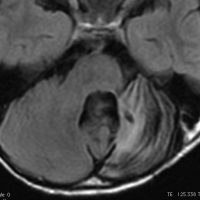

3歳の子どもの髄芽腫の放射線治療後に生じた脳萎縮

3歳の髄芽腫です。発症時から小脳表面や小脳橋角部を含めて転移がありました stage M2。化学療法で腫瘍はかなり縮小して,3歳7ヶ月まで頑張ってから,後頭窩照射 25.2グレイ14分割と脳脊髄照射 CSI 28.8グレイ16分割の放射線治療をしました。当時このような例では,脳脊髄照射 36グレイが標準治療でしたから,これでもかなり線量を落としました。

左側の画像は照射後4ヶ月目です。延髄の左側に放射線壊死が生じました。これは数ヶ月かかってゆっくり消褪しました。右側の画像は照射後1年くらいのものです。大脳白質にびまん性に萎縮性変化がみられます。典型的な放射線治療による白質萎縮です。この程度の線量でも脳壊死や全脳萎縮を生じない子どももいます。

放射線の副作用は同じ線量でも個人差がとても大きいです idiosyncrasy